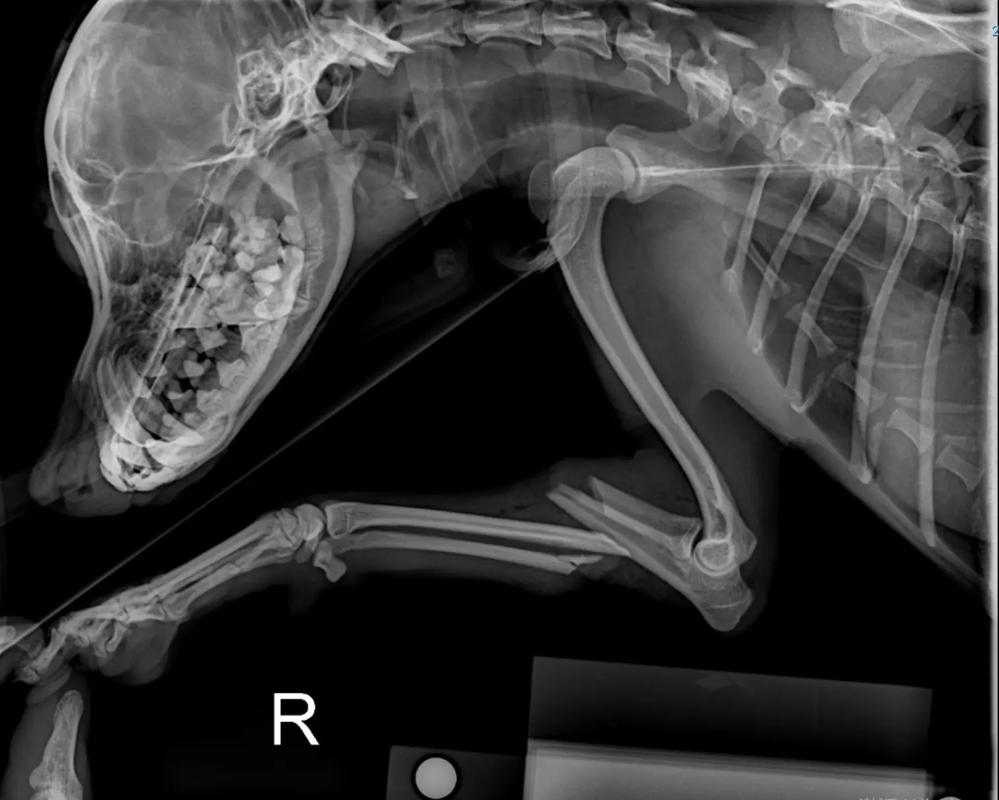

如果骨折部位发生错位或者骨折比较严重,可能会导致肢体弯曲、变形、延长和肿胀,轻轻晃动的时候能听到骨头的摩擦音,这是比较明显的症状。如果宠主怀疑狗狗骨折了,建议及时带它去宠物医院拍片检查,如果确定是骨折,需要及时进行外固定或手术治疗。

在为狗狗检查时需确保安全,因为疼痛可能会使狗狗咬人。 观察狗狗的行走方式,如果出现跛行或不愿让脚着地等异常行为,可能是骨折的表现。 通过X光片检查是最准确的方法,可以清晰地看到是否发生骨折。 触摸狗狗的腿骨,检查是否有明显的断裂或错位感。